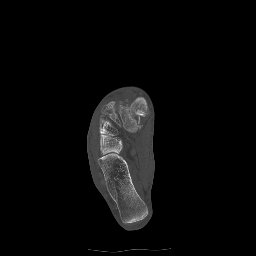

Return to Lisfranc Fracture-Dislocation